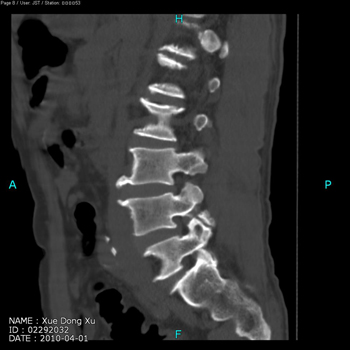

男,62岁,诊断:腰椎滑脱(L4,I度),峡部裂

术前CT